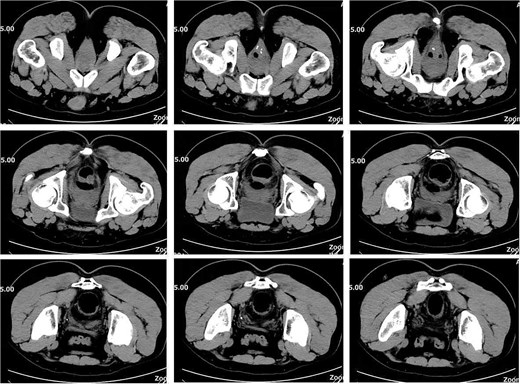

On postoperative Day 10, a repeat complete blood count showed a white blood cell count of 9.74 × 109/l and a neutrophil percentage of 69.5%. The patient’s temperature ranged between 36.4 and 37.4°C, and abdominal discomfort was partially alleviated. A follow-up pelvic CT scan revealed a breach in the anterior rectal wall with gas density shadows communicating with the surrounding area, accompanied by filamentous exudate density shadows and multiple gas density shadows (Fig. 2). These findings indicated rectal wall edema and anterior wall perforation with surrounding infection. Anorectal examination revealed a 0.5 × 0.5 cm ulcerative lesion at the 5 o’clock position of the anastomosis site in the knee–chest position. This was considered rectal perforation secondary to anastomotic dehiscence. Given the absence of peritoneal irritation signs and normalization of the white blood cell count, a conservative treatment plan was adopted after discussion with the patient. This plan involved continuing anti-infective treatment with intravenous cefoperazone sodium and sulbactam sodium.